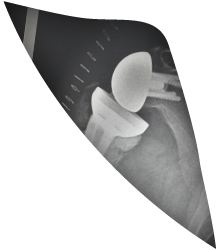

תמונה מחדר ניתוח תמונת פרופיל

עוסק בעיקר בבעיות ומחלות של מפרק הכתף. מומחה  בארתרוסקופיות של הכתף הכוללות ניתוחים לייצוב הכתף ותיקון גידים, פציעות ספורט וטראומה של הכתף, שברים של עצם הכתף ועצם הבריח וכן בהחלפות מפרק הכתף (משתלים).

תמונת כתף